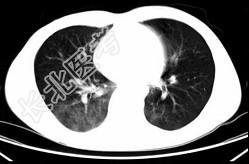

- 单项选择题男,35岁, 被车撞伤后1小时,结合影像图像选择其最可能的诊断为 ( )

D、肺挫伤